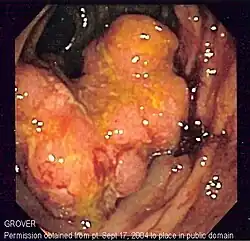

Los cánceres del intestino grueso se conocen con el nombre genérico de «cáncer colorrectal», a pesar de que hay una serie de diferencias entre el cáncer de colon y el cáncer rectal. De hecho, parece que también hay diferencias significativas entre los cánceres del colon derecho y los del colon izquierdo, cosa que ha llevado algunos investigadores a afirmar que, en realidad, son dos patologías distintas.[26]

El cáncer colorrectal es el tercer cáncer que mata más gente en el mundo, después del cáncer de pulmón y el cáncer de mama.[27] Esto es debido de no tanto a su mortalidad relativamente moderada[28] como su alta incidencia en la población. Este tumor se encuentra entre los tres más comunes en la mayoría de países desarrollados, cosa que hace que mate más gente que otros cánceres más letales pero menos comunes.

Una de las cosas que hacen que el cáncer colorrectal mate tanta gente es que a menudo es diagnosticado cuando la enfermedad ya está avanzada.[29] Como otros muchos cánceres, no suele dar síntomas hasta que ya ha metastatizado y es incurable en la gran mayoría de casos. Las autoridades sanitarias han llevado a cabo campañas de sensibilización sobre la importancia que las poblaciones de alto riesgo de cáncer colorrectal (gente de más de 45 años,[30] gente con antecedentes de este cáncer en la familia, gente con ciertas mutaciones genéticas y gente que sufre de enfermedades inflamatòries intestinales desde hace muchos años[31]) se hagan pruebas de diagnóstico periódicamente para detectar cualquier tumor antes de que se haya esparcido. Parte de este trabajo de sensibilización se ha concentrado al hacer entender a la gente que no se tiene que esperar a tener síntomas, puesto que entonces a menudo es demasiado tarde. Las pruebas más utilizadas para detectar el cáncer colorrectal son la prueba de detección de sangre en heces (más barata y fácil de hacer, pero menos eficaz)[32] y la colonoscopia, que es la estándar de referencia por el diagnóstico de este tumor.[33]

- Pólipos del colon